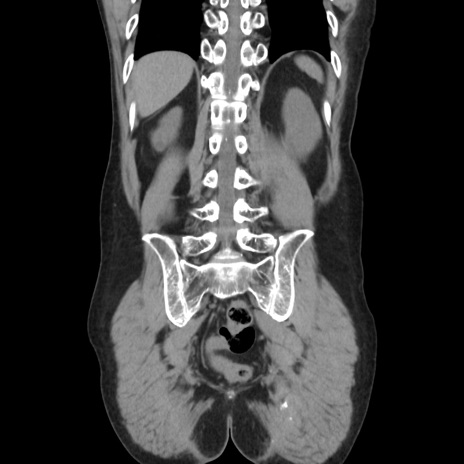

症例37(冠状断像)

【症例】40歳代 男性

【主訴】腹痛

【現病歴】4時間ほど前に電車に乗車中に臍部上より腹痛出現。徐々に増悪し起立困難となり、救急外来受診。生ものは数日食べていない。今朝お雑煮を食べた。

【身体所見】BT 36.8℃、BP 117/84mmHg、HR 91/min、SpO2 97%、苦悶様、腹部:臍上部広範囲圧痛あり、反跳痛±

【データ】WBC 8100、CRP 0.03